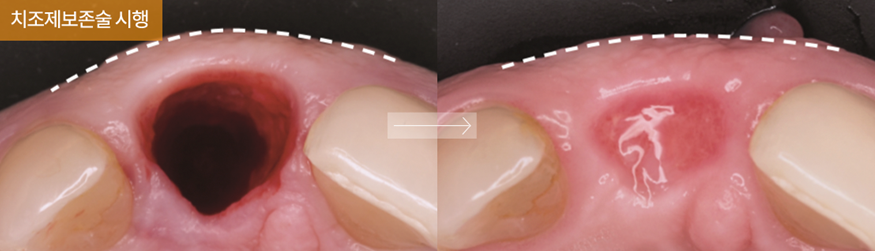

- i-GBR (치조제보존술)

![임플란트 부작용 자세히 알아보기(3) 임플란트 치주조직손상 부작용 [ 예방 및 대처 방법 ] [ 강남새로치과 ] 관련 이미지 5](https://pub-9f2bb3498faf4d1d8714b41df24753e3.r2.dev/content/clinics/archive/vfz5midfrl/naver_blog/saerodental8522/assets/by_hash/094683b3ac2ba342bf5c38cfd1c21d52e7a51065b9eeb35b5a9db81cd6874599.png)

발치 즉시 행할 수 있는 치주조직 재생입니다. 발치 후 36개월 내에 34mm 정도의 치은과 치조골 퇴축이 발생하는데 치조제 (치조골의 능선 부분) 보존을 하지 않게 되면 치은과 치조골의 퇴축이 그대로 발생하여 임플란트 식립이 어려운 지경에 이릅니다.

![임플란트 부작용 자세히 알아보기(3) 임플란트 치주조직손상 부작용 [ 예방 및 대처 방법 ] [ 강남새로치과 ] 관련 이미지 6](https://pub-9f2bb3498faf4d1d8714b41df24753e3.r2.dev/content/clinics/archive/vfz5midfrl/naver_blog/saerodental8522/assets/by_hash/28df974729f75afac38527f7fd1cd1860ccc9afba71308889bc82b321e3fee7f.png)

대학병원식 골이식술 발치즉시 골이식술(i-GBR)인 치조제보존술을 진행하면 발치 부위에 골이식재와 천연 콜라겐막을 보충하므로 임플란트 수술 후에도 치은의 볼륨감과 단단함을 오래 지속시킵니다.